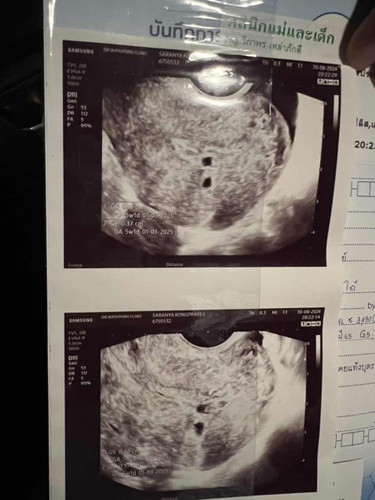

ฝากครรภ์5wเจอถุงครรภ์แฝด

ฝากครรภ์5wเจอถุงครรภ์แฝด หมอนัดอีกตอน6w4dน้องโตแค่ถุงเดียว อีกถุงนึงไม่โตกลัว วันที่18สิงหา หมอนัดตรวจคัดกรองดาวน์ซินโดม ตอนนี้กลัวมากค่ะ กลัวว่าอีกคนที่เหลืออยู่จะไม่แข็งแรง แม่อายุ39ย่าง40แล้วค่ะ เคยท้องนอกมดลูก1ครั้ง และท้องต่อมาน้องก็หยุดหายใจตอน6w กลัวไปหมดแล้วตอนนี้